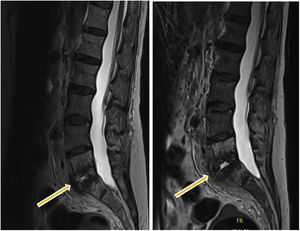

Fue trasladada a un centro de rehabilitación neurológica de nuestra comunidad. Treinta días después presentó nuevamente bacteriemia por S. marcescens de origen no filiado, descartándose endocarditis mediante ecocardiogramas transtorácico y transesofágico y fue tratada con ertapenem intravenoso durante 14 días. Tras 4 meses, inició dolor lumbar irradiado a pierna izquierda que no cedía con tratamiento analgésico. Se realizó RMN con hallazgos compatibles con EI (L5-S1). Ingresó en el servicio de enfermedades infecciosas de nuestro hospital para estudio etiológico y tratamiento. Se obtuvieron 3 biopsias guiadas por TAC, cuyo cultivo aerobio/anaerobio/prolongado en medio de enriquecimiento/micobacterias y PCR del gen ARNr 16S resultaron negativos. Durante el ingreso se extrajeron hemocultivos seriados con resultado negativo.

Tras 8 semanas con antibioterapia empírica de amplio espectro, que consistió en una terapia combinada intravenosa de cefepime y daptomicina, no presentó mejoría clínica, y en la RMN se halló empeoramiento radiológico (fig. 1). Se decidió realizar una biopsia quirúrgica abierta, y se enviaron 9 muestras a nuestro servicio de microbiología.